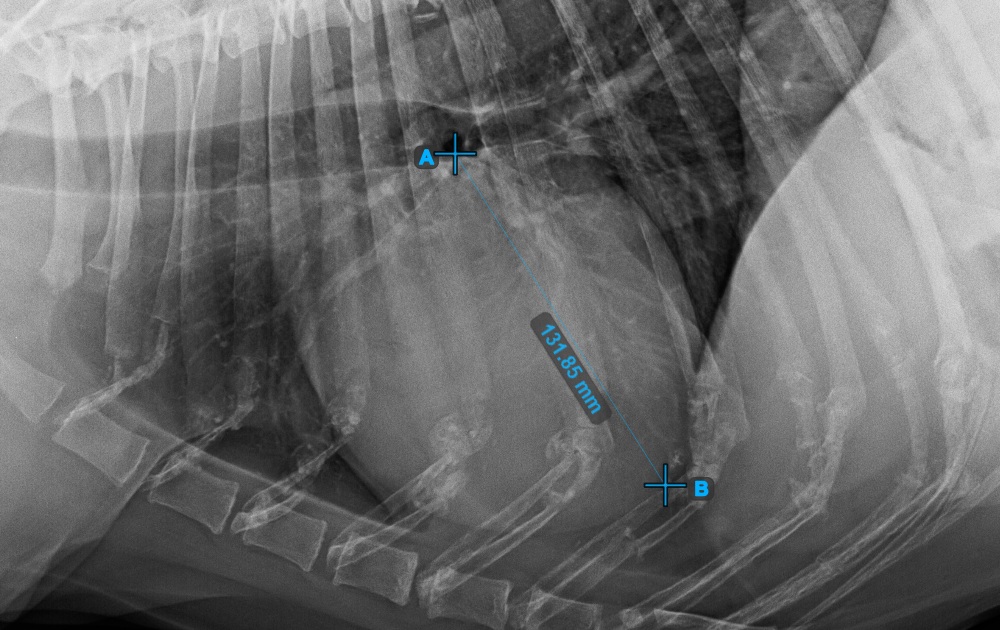

Continue the measurement by marking the widest right (cranial) point of the short axis of the heart.

The image below represents a typical placement of the most cranial point on the short axis of the heart.

../../_images/image395.jpg

Complete the short axis of the heart by marking the widest left (caudal) point.

The image below represents the typical placement of the most caudal point on the short axis of the heart.

../../_images/image396.jpg